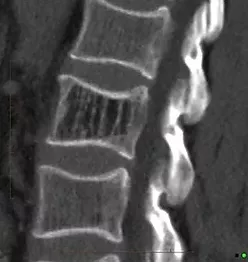

Компьютерная томография является основным методом диагностики диагностики гемангиом позвонков. Она позволяет определить размеры, распространенность, выраженность изменений костной ткани, провести дифференциальную диагностику гемангиом. Главным рентгенологическим признаком гемангиом является специфическая перестройка губчатого вещества тела позвонка, заключающаяся в сочетании частичного лизиса костной ткани с гипертрофией сохранившихся костных трабекул. На аксиальных срезах тело позвонка напоминает "пчелиные соты".